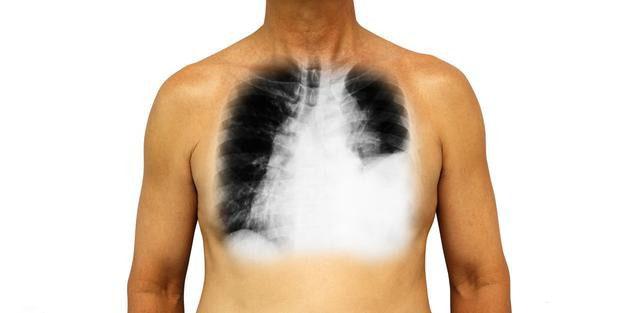

在门诊遇到不少这样的肺癌病人,说自己受凉了,嗓子哑了,而且逐渐加重,有些病人先去耳鼻喉科看,没有发现咽喉、声带发炎。这类病人我们一听声音,就知道可能不妙,肿瘤转移的可能性很大。

约有 20%~30%的肺癌病人在疾病的不同时期甚至早期内出现声音嘶哑,其中中央型肺癌可高达 40%。这种声音嘶哑常发生比较突然、进展迅速、甚至完全失声,同时大多数病人伴有胸痛、咳嗽等症状,经抗炎对症治疗两周以上仍无效果。

肺癌患者出现声音嘶哑一般考虑肿瘤直接压迫喉返神经或者转移至纵膈淋巴结压迫喉返神经引起。因为喉返神经是支配声带运动的,当喉返神经受损,会引起声带麻痹,声带麻痹可导致一侧声带固定不动或运动产生障碍,主司发音的声带不可能闭合,从而呈现声音沙哑。左侧喉返神经从主动脉弓和左侧主支气管之间开始,在胸腔内行走的距离比右侧喉返神经长。因此,相比右侧,左侧喉返神经更容易受胸部病变的影响。一般而言,当喉返神经受到侵犯,出现声音嘶哑时,可认为肺癌已经发展到晚期。